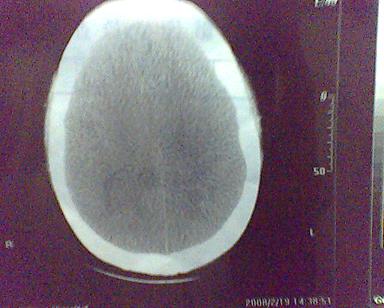

男 31岁 短暂性四肢抽搐 呼叫不应  头胀痛4个多月 无发热 4年前遭棒击头部,当时未到医院检查。余无特殊。病人特穷,未作增强。

这是一个边缘清晰的等密度的囊性占位.密度比较均匀,周围无水肿,我顷向于脑脓肿的可能性大.